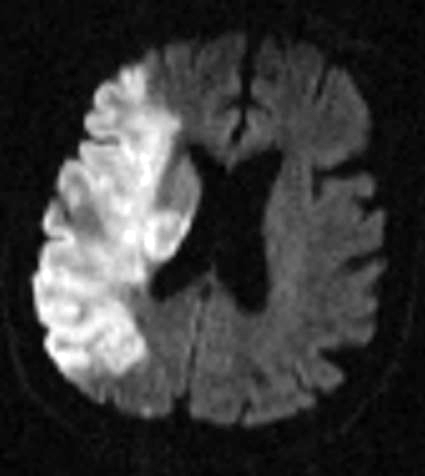

Figure 1: Ischemic Stroke. In an early acute ischemic cerebral stroke, a common finding is a normal CT scan since the brain tissue has not yet begun showing ischemic changes (left image). The middle image shows a diffusion weighted image (DWI) of a right hemispheric stroke (white area), and a CT angiogram shows the cause to be a blockage of the right middle cerebral artery (MCA), seen as a lack of blood vessel flow on the right side of the brain (left side of image). Poor blood flow is also seen in the right internal carotid artery due to stenosis from atherosclerosis. (Images courtesy of Dr. McMurtrey)